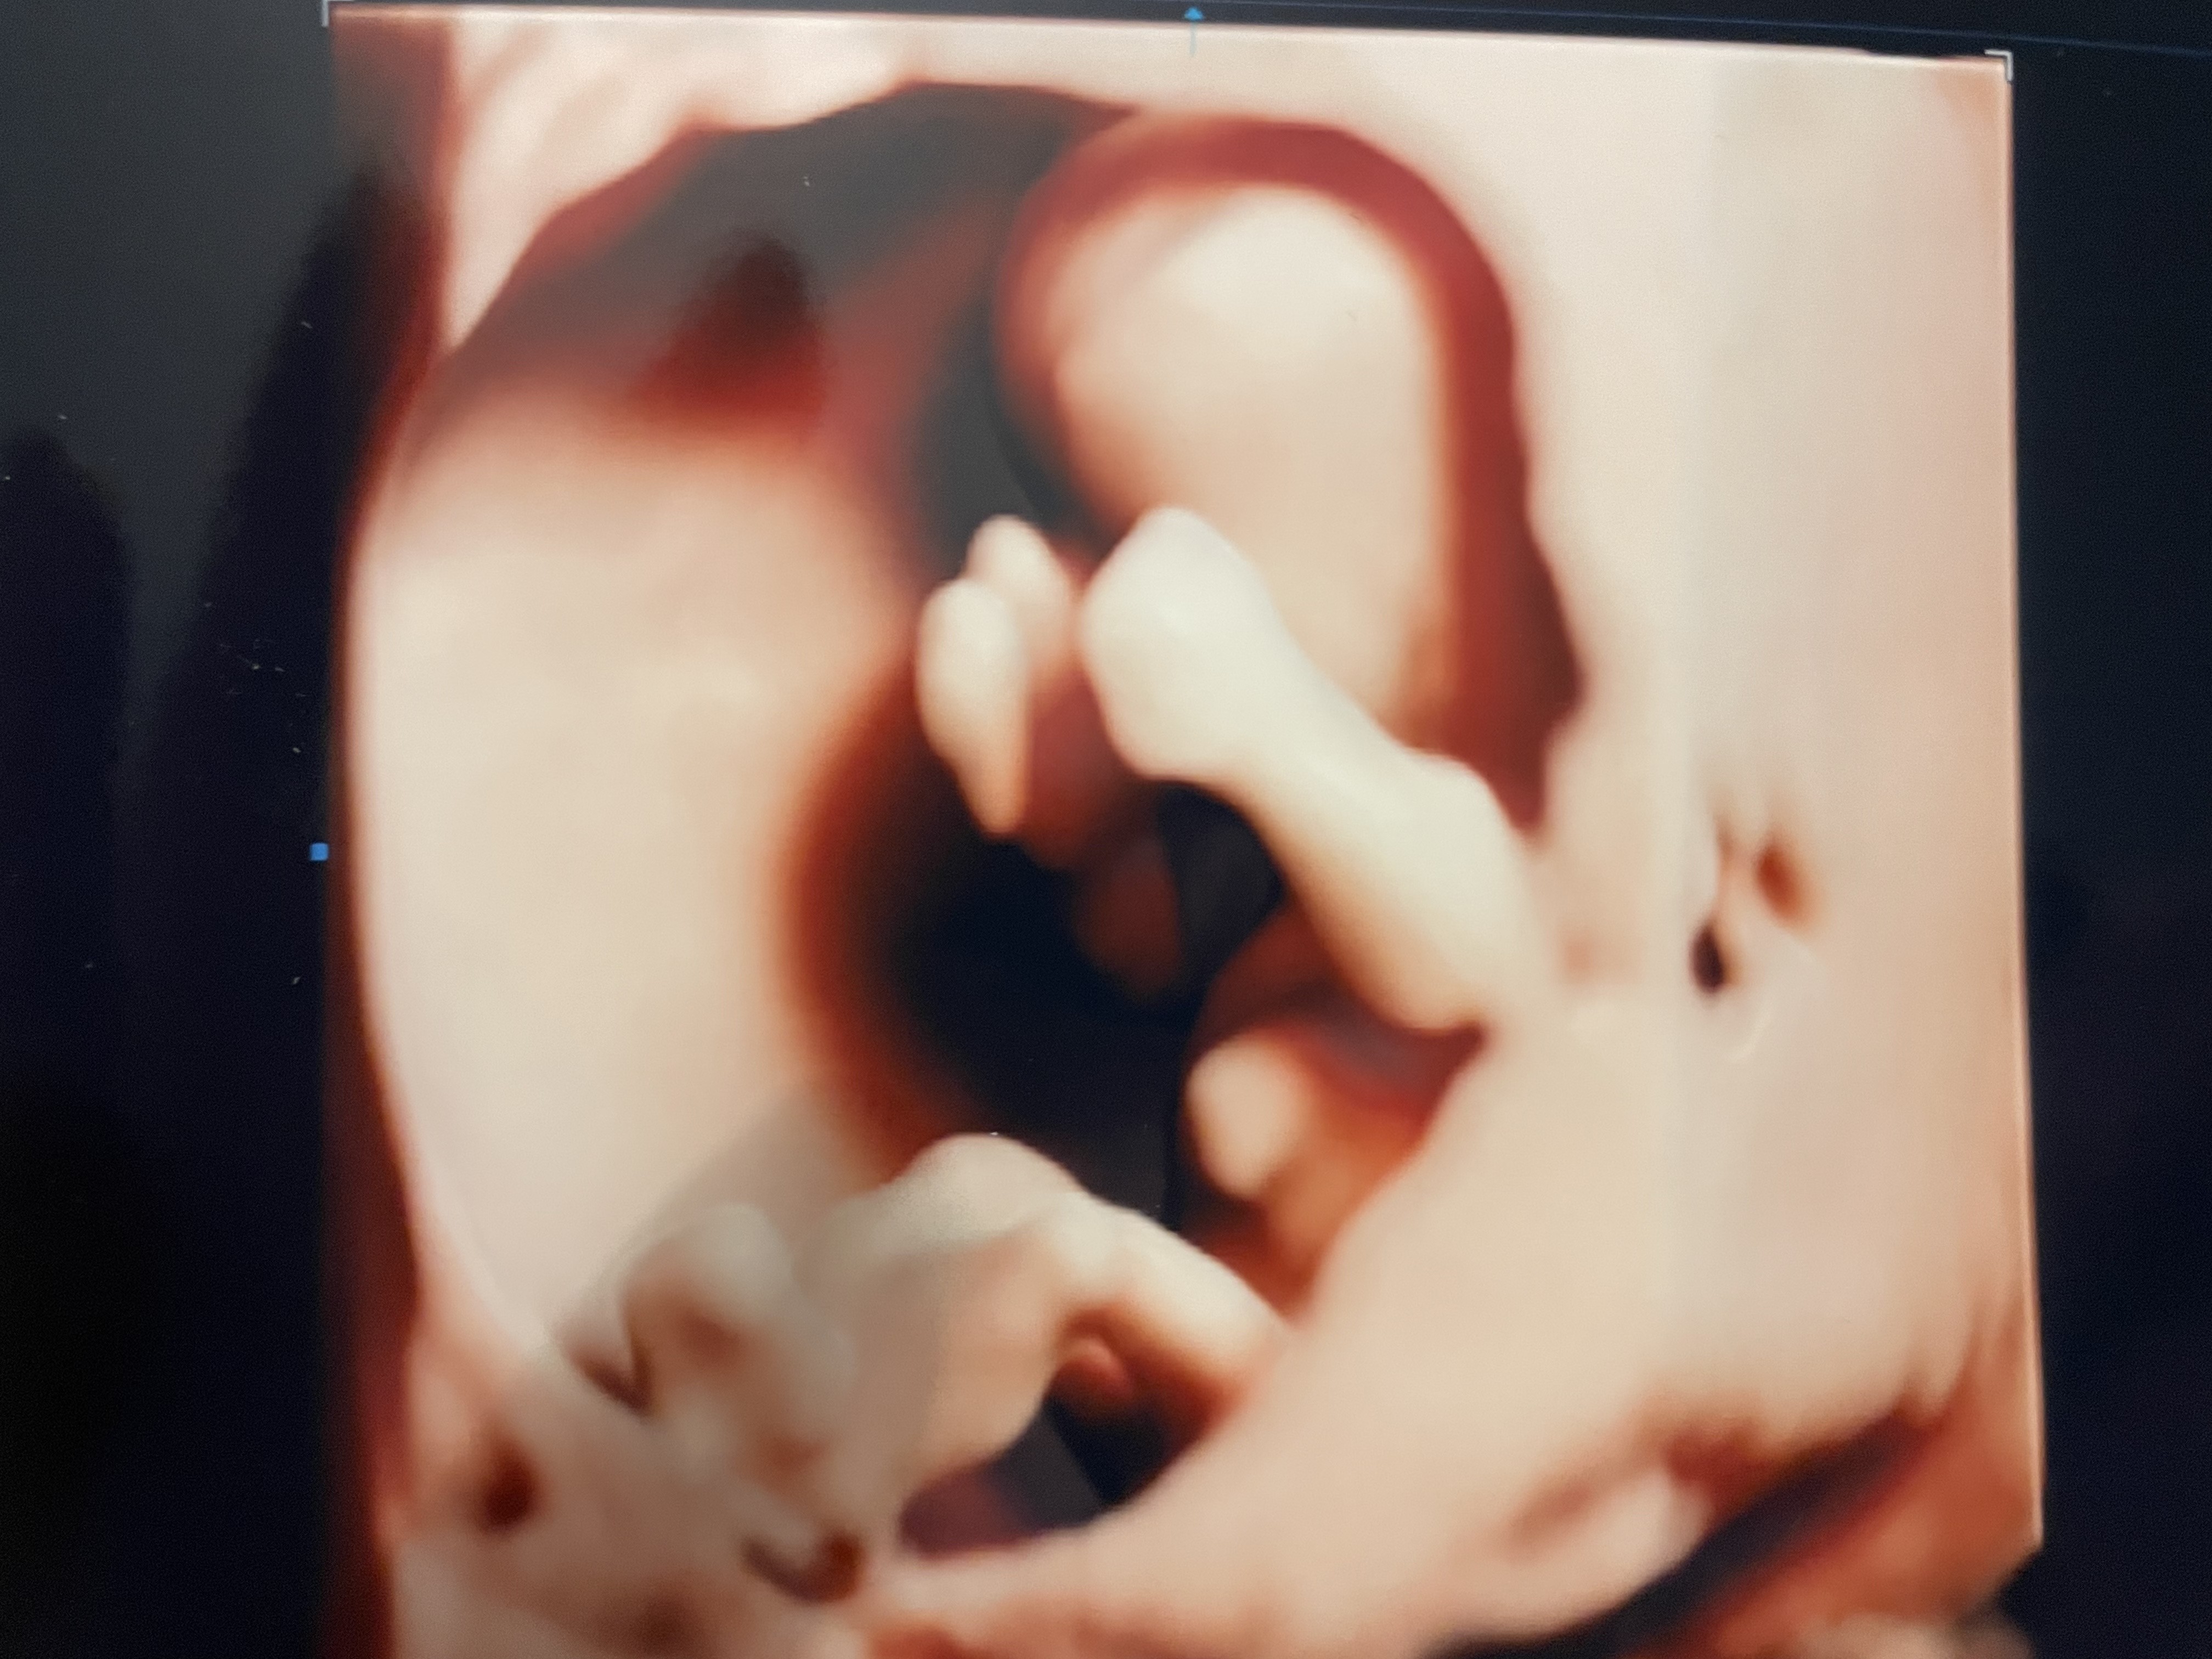

Cześć Dziewczyny, bardzo Was przepraszam, ale miałam dziś taki dzień, ze jeszcze nie dotarłam do domu! Już Wam wszystko opisze o moich badaniach prenatalnych. Po pierwsze byłam na takich prywatnych badaniach, które sprawdzają nie tylko podstawowe trisomnie i wady genetyczne, ale analizują całe dziecko anatomicznie od głowy do stop. U mnie wszystko jest super. Głupio mi o tym pisać w kontekście tego, co wydarzyło się dziś u Pszczółki, ale mam nadzieje ze da to Wam wszystkim nadzieje. Moja córka - okazało się ze to dziewczyna

- rośnie jak na drożdżach i znowu jest większa niż zakładany tydzień z ostatniego usg- aktualnie ma wymiary na 14 tydzień i był to ostatni moment na badanie 1. Trymestru. Termin porodu tez na ten moment przesunął mi się na 28 czerwca, ale mam nadzieje ze nie wydalicie mnie z grupy, bo się z Wami zżyłam :-) Lekarz sprawdził przepływy dziecka w wątrobie, sercu i mózg, pokazał wszystkie narządy, pomierzył bardzo dużo rzeczy i opisał wynik na 2 strony stwierdzając, ze jest wszystko super! Powiedział tez, jeśli chodzi o badania z krwi pappa, ze to jest tylko badanie pomocnicze i absolutnie nie jest ani miarodajne ani do końca wiarygodne i nie należy do niego przywiązywać wagi (co ponoć robi się na Fundusz, bo taka jest procedura, stad tak wiele biopsji kosmowki, gdzie wszystko wychodzi ok). Dostałam zdjęcia i dostałam film z nagraniem całego przebiegu badania z analiza tych wszystkich organów. Zapłaciłam za wizytę 400 zł i uważam, ze były to super wydane pieniądze. Jak ktoś jest z Krakowa lub okolic to mogę polecić z czystym sumieniem to miejsce :-) choć sam profesor jest specyficzny w odbiorze i kontakcie, ale jest mega specem od usg płodów :-) spróbuje Wam zaraz podłączyć jakaś fotkę :-) i jak macie jakieś pytania to piszcie!